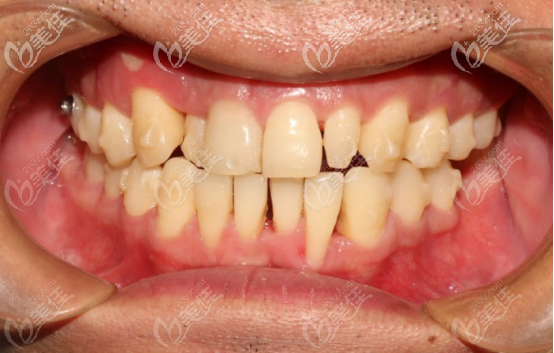

術(shù)前正面照

術(shù)前口內(nèi)照

術(shù)前自我認為的牙齒問題:

牙列擁擠,不整齊,缺牙,牙齒歪斜,有兩個過于小的牙齒,影響咀嚼。

1、安氏I類(上頜的恒磨牙咬住下頜恒磨牙,其他牙齒咬合均異常)

2、骨性III類(俗稱的地包天)

3、牙弓尖圓形(牙弓的整個輪廓呈現(xiàn)前尖后圓型,正常是橢圓形)

4、上下頜前牙中度擁擠

5、過小牙(錐形牙,牙齒發(fā)育不全)

6、前牙區(qū)對刃(就是前牙的咬合無法覆蓋)

7、牙齒反頜(就是下牙咬在了上牙的外面)

8、殘根(齲壞將牙齒腐蝕后剩下的部分)

9、埋伏多生牙(多長出來的牙齒,埋伏在牙槽骨里面很深的位置)

10、上下中線均右偏(牙齒歪斜)

這是顱面的側(cè)位直面型照片,可以很明顯的看出有輕度的地包天現(xiàn)象。